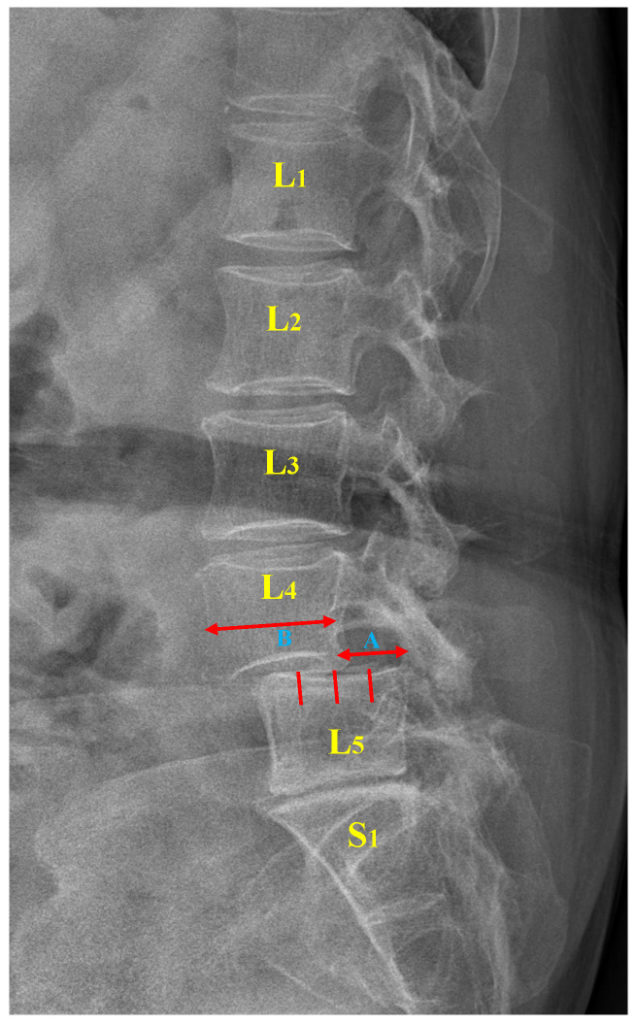

Spondylolisthesis

Spondylolisthesis occurs when a vertebra slips, usually forward, on the vertebra below, causing narrowing of the spaces for the spinal cord and spinal nerves as they exit the spine.

This condition can cause sciatica depending on the severity. An osteopath can assess your back to see if you have a ‘step defect’ and refer you for an X-ray of your spine to confirm the diagnosis.[11]